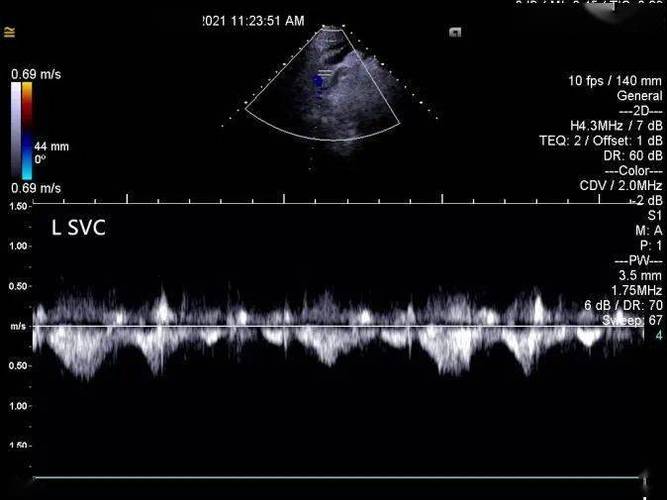

图 4 彩色多普勒超声示左位上腔静脉呈蓝色血流信号图 3 胸骨上窝切面